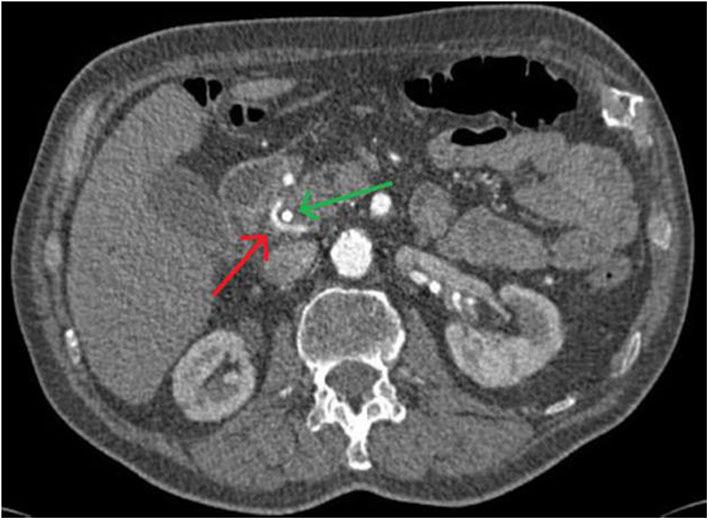

Bühler's anastomosis (or Bühler's arcade) is an embryonic relic and represents an arterio-arterial connection between the superior mesenteric artery and the celiac trunk. It can be found as a variety in 1-2% of patients. We present a case of a patient with metatastatic squamous cell carcinoma of the lung. The patient was in stable disease for 4 years under palliative therapy (most recently second-line therapy with Nevolumab). In 2019, a locally advanced adenocarcinoma of the papilla vateri was diagnosed, additionally. The patient also underwent right hemicolectomy and patch plasty of the celiac trunk and superior mesenteric artery due to colonic ischemia and arteriosclerotic disease with 50-70% stenosis of the superior mesenteric artery several years ago. Due to a complex vascular prehistory, the standardized preoperative imaging was supplemented by two independent vascular reconstructions (a CT angiogram and a reconstruction based on the CT) for the planning of a pylorus-preserving pancreatic head resection and reconstruction according to Traverso-Longmire. In addition, a 3D print was produced. Both, the reconstruction based on the CT scan and the 3D print were created for off-label use as a part of a research project (VIVATOP: Versatile Immersive Virtual and Augmented Tangible OP). In the standardized CT scan and in the clinical CT-angiography, there were no obvious surgically relevant anatomical variations. A Bühler anastomosis was detected in a digital, virtual and interactive 3D-reconstruction. In addition, in the 3D print of the abdominal site the anastomosis was seen as well. Intraoperatively, the presence of Bühler's anastomosis was confirmed. This information had a significant impact on the intraoperative approach. Retrospectively, the vessel variant could be surmised in the axial projection of the CT scan, if one knew what to look for. For the conduction of a safe surgical procedure, it is imperative that rare anatomical variations are known preoperatively. Increasing digitalization in surgical and perioperative preparation holds great potential for better planning and improved patient safety. Research and cooperation projects such as the VIVATOP project are instrumental for the development of new visualization techniques, which are able to enhance the understanding of complex anatomical relations.

比勒吻合术(或比勒血管弓)是一种胚胎遗迹,代表肠系膜上动脉与腹腔干之间的动脉-动脉连接。在1%-2%的患者中可发现其存在多种类型。我们报告一例肺转移性鳞状细胞癌患者。该患者在姑息治疗(最近为纳武单抗二线治疗)下病情稳定4年。此外,2019年诊断出壶腹周围局部晚期腺癌。几年前,该患者还因结肠缺血和动脉硬化性疾病,肠系膜上动脉狭窄50%-70%,接受了右半结肠切除术以及腹腔干和肠系膜上动脉补片成形术。由于血管病史复杂,在根据特拉弗索-朗迈尔法进行保留幽门的胰头切除和重建手术规划时,标准化的术前影像通过两次独立的血管重建(一次CT血管造影和一次基于CT的重建)进行补充。此外,还制作了一个3D打印模型。基于CT扫描的重建和3D打印模型均作为一个研究项目(VIVATOP:多功能沉浸式虚拟和增强实体手术)的一部分用于非标签用途。在标准化CT扫描和临床CT血管造影中,未发现明显的与手术相关的解剖变异。在数字化、虚拟和交互式3D重建中检测到了比勒吻合术。此外,在腹部区域的3D打印模型中也看到了该吻合术。术中证实了比勒吻合术的存在。这一信息对术中操作方法产生了重大影响。回顾性分析,如果知道要寻找什么,在CT扫描的轴向投影中可以推测出血管变异。为了进行安全的外科手术,术前了解罕见的解剖变异至关重要。手术和围手术期准备中日益增加的数字化对于更好的手术规划和提高患者安全性具有巨大潜力。像VIVATOP项目这样的研究与合作项目有助于开发新的可视化技术,能够增强对复杂解剖关系的理解。